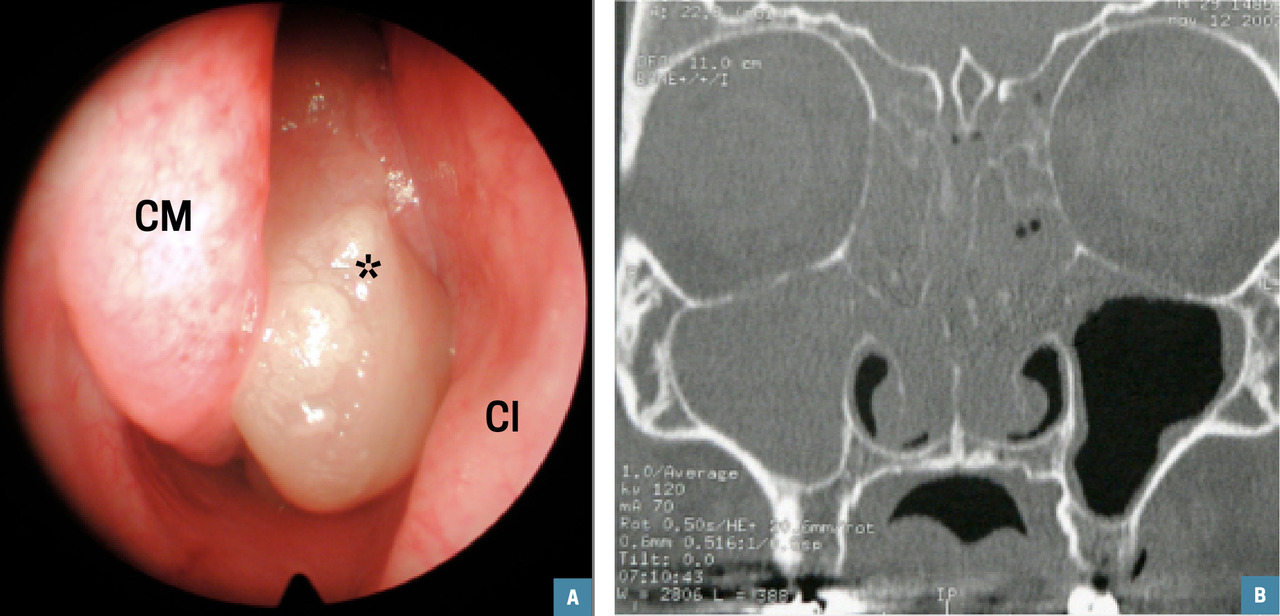

Avec polypes (figure)

Les glucocorticoïdes nasaux, par rapport au placebo, diminuent significativement les symptômes, la taille des polypes, le risque de récidive, et augmentent le débit inspiratoire nasal maximal, qu’ils soient de nouvelle (mométasone, fluticasone) ou de première génération (budénoside, béclométasone, triamcinolone). La réduction de volume des polypes est d’autant plus importante s’ils siègent dans une cavité nasale opérée.